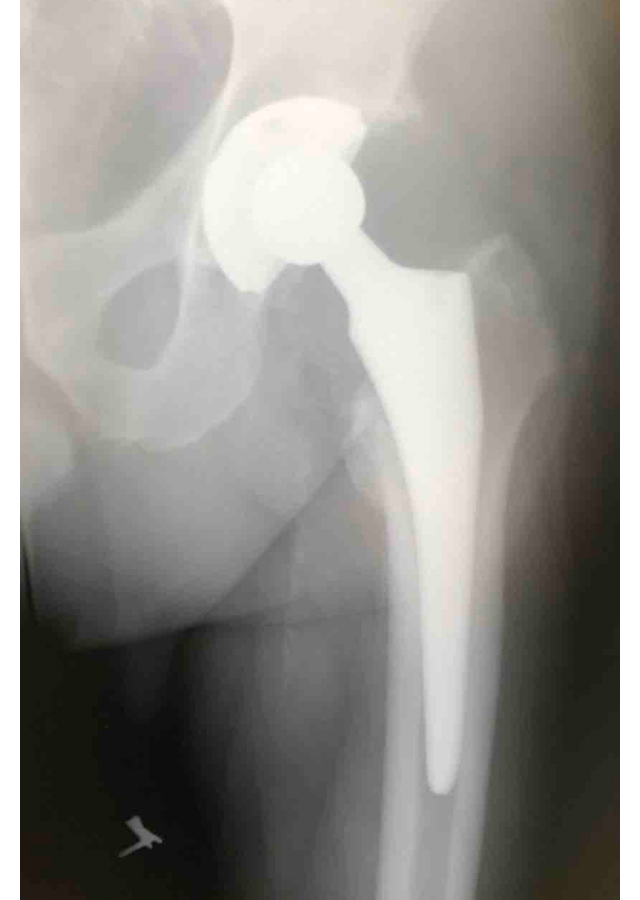

Csípő és térd ízületi betegségek protetizálása

Degeneratívtól, posttraumáson át veleszületett deformitásokig, revíziók, egyszerű és bonyolult helyzetek megoldása.